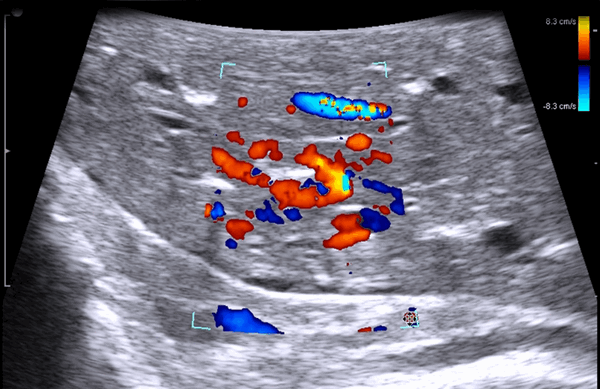

В случае выявления образований в печени и измененных забрюшинных лимфатических узлов (при необходимости) выполняли пункционно-аспирационную биопсию. При этом образование, эхографически подозрительное на метастатический узел, располагалось по центру сканирующей поверхности датчика и тем самым по центру монитора. При исследовании обязательно использовали методику допплерографии для выбора участков с наименьшим кровоснабжением. Эта же методика позволяла визуализировать кровеносные сосуды над узловым образованием и избежать их повреждения. После выполнения указанных моментов выполняли непосредственно пункцию.

У 5 (41,7%) из 12 пациенток образования в печени имели гиперэхогенную, гомогенную структуру с четкими и ровными контурами размером от 5 до 12 мм в диаметре, которые были интерпретированы как доброкачественные образования печени — гемангиомы (табл. 2). У 4 (33,3%) пациенток образования имели анэхогенную гомогенную структуру, с четкими и ровными контурами, с гладкой внутренней выстилкой и эффектом усиления эхосигнала, размером от 3 до 11 мм в диаметре, и были интерпретированы как кисты. В 3 (25%) случаях в печени были выявлены гипоэхогенные образования солидной гетерогенной структуры с нечеткими, но ровными контурами размером от 10 мм в диаметре (рис. 1) до 22×17×15 мм в одном случае, расположенное на диафрагмальной поверхности печени, которое «самоампутировалось» в процессе исследования и при срочном гистологическом исследовании оказалось метастазом аденогенного рака (рис. 2).

Рис. 1. Эхограмма. Интраоперационное УЗИ печени (стрелкой указан метастаз рака яичника).